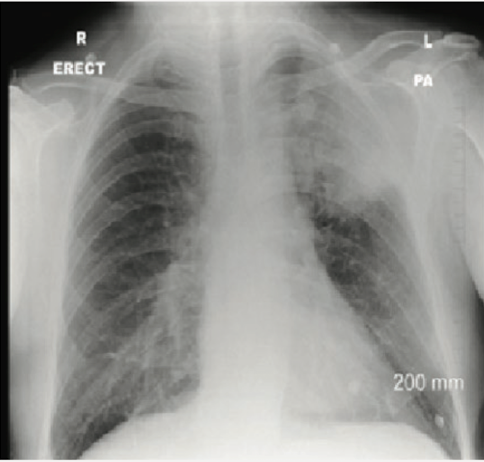

Q

Describe the CXR.